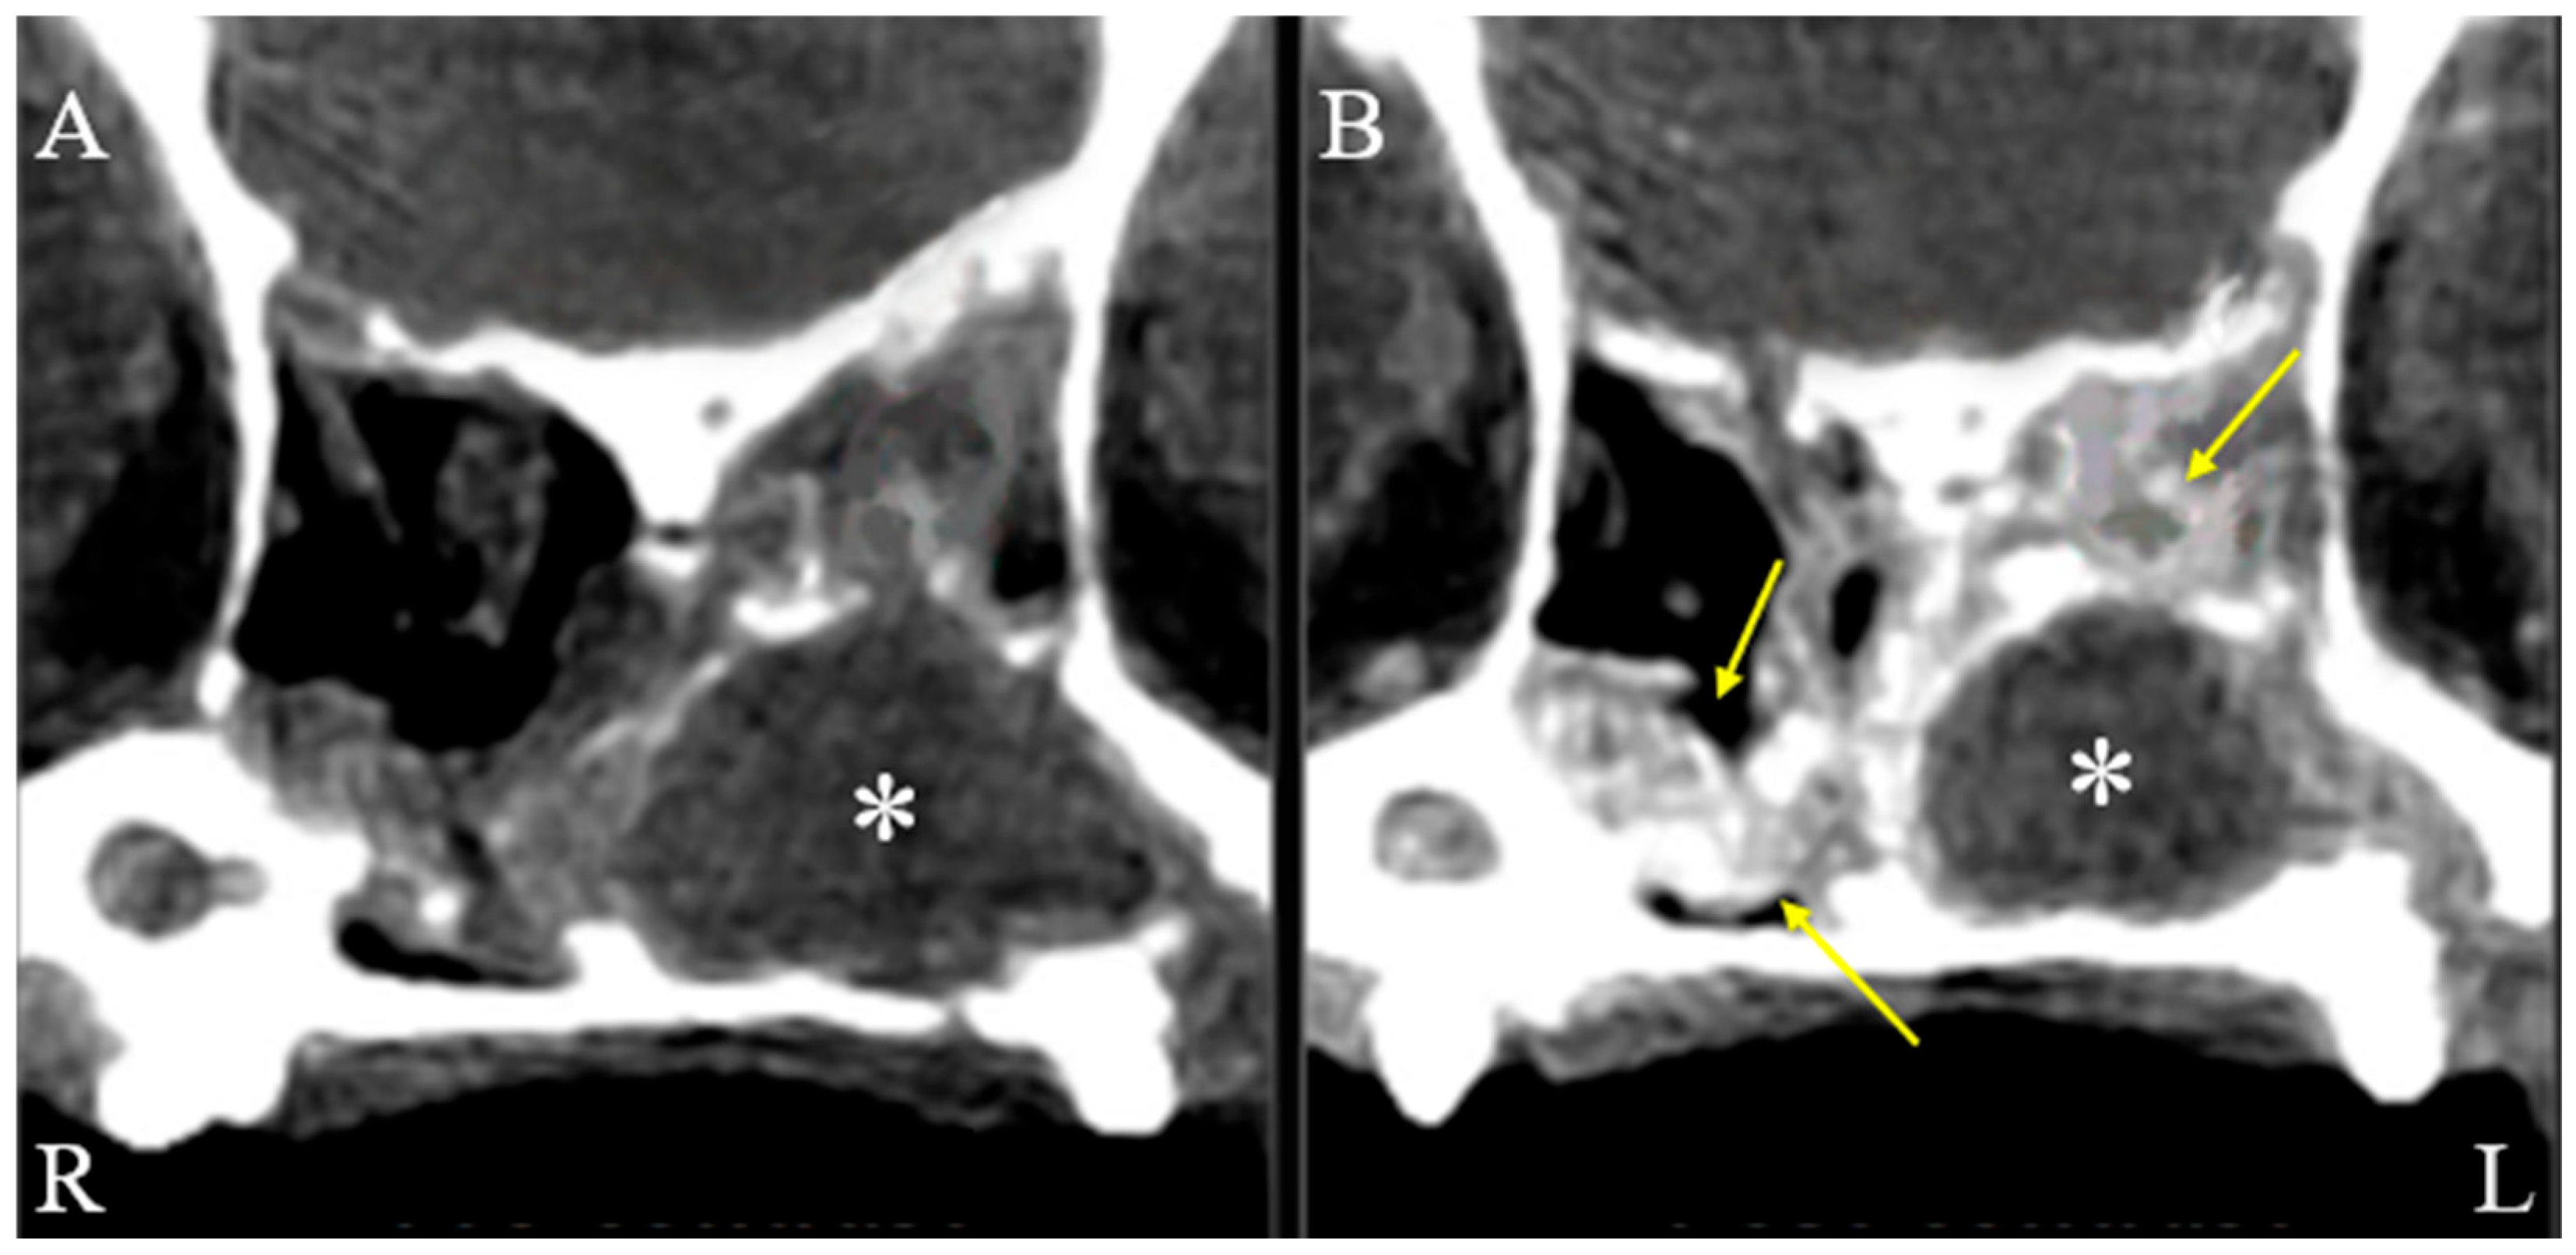

On physical examination, the dog showed serous nasal discharge in the left nasal cavity, nasal congestion, and intermittent reverse sneezing. Other physical examinations were unremarkable. Based on these findings, further computed tomographic (CT) evaluation of the nasal cavity was required. The dog was premedicated with butorphanol (0.2 mg/kg, intramuscular injection, Myungmoon, Seoul, Republic of Korea). Anesthesia was induced with propofol (6 mg/kg, intravenous injection, Myungmoon, Seoul, Republic of Korea). Intubation was performed, and anesthesia was maintained with isoflurane. CT (MyVet CT i3D, Woorien, Seoul, Republic of Korea) images of the nasal cavity were obtained. CT findings revealed a fluid-attenuated structure measuring 1.35 × 1.68 × 1.49 cm located in the mid-region of the left nasal cavity. The lesion involved the left nasal cavity, accompanied by soft tissue swelling in the adjacent left perinasal region, suggesting possible pathology in both the nasal cavity and surrounding soft tissues (Figure 1). The scan also revealed a fluid-attenuated mass occupying the nasal cavity, with evident contrast enhancement in the adjacent soft tissues, indicating pathological involvement of the surrounding structures (Figure 2).

Figure 2. Axial, soft tissue window, pre (A) and post (B) contrast CT images of the dog’s nasal cavity. Axial soft tissue window CT images of a dog’s nasal cavity (R: right, L: left), comparing pre-contrast (A) and post-contrast (B) scans. Surrounding the mass (asterisks), soft tissue-attenuated structures with contrast enhancement (arrows) are visible within the nasal cavities, indicating soft tissue changes adjacent to the mass.